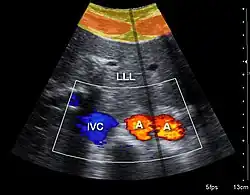

Doppler ultrasonography is used to study blood flow and muscle motion. The different detected speeds are represented in color for ease of interpretation, for example leaky heart valves: the leak shows up as a flash of unique color. Colors may alternatively be used to represent the amplitudes of the received echoes.

Doppler ultrasonography employs the Doppler effect to assess whether structures (usually blood)[58][61] are moving towards or away from the probe, and their relative velocity. By calculating the frequency shift of a particular sample volume, flow in an artery or a jet of blood flow over a heart valve, its speed and direction can be determined and visualized, as an example. Color Doppler is the measurement of velocity by color scale. Color Doppler images are generally combined with gray scale (B-mode) images to display duplex ultrasonography images.[62] Uses include: